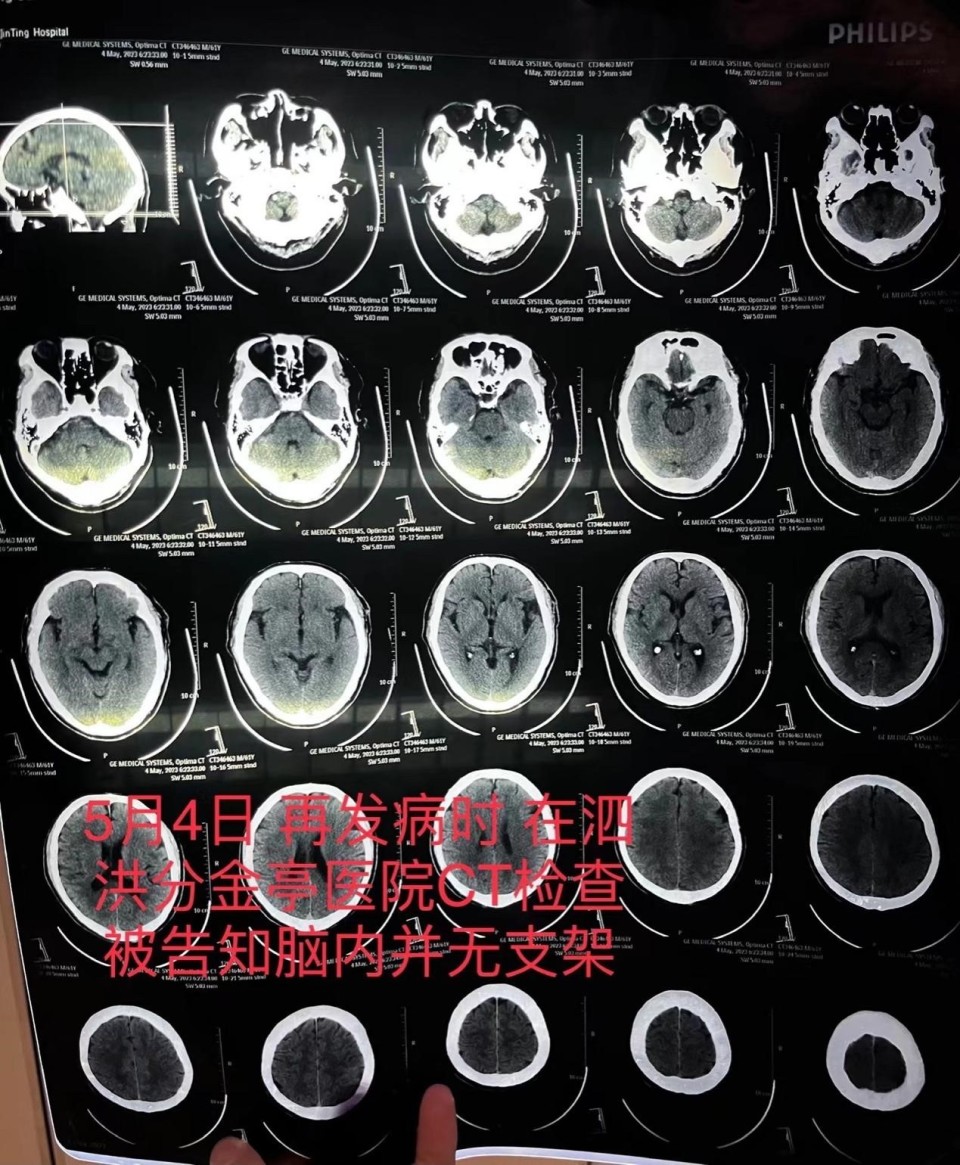

5月4日,朱老汉突发严重脑梗。他先被救护车送至江苏省宿迁市泗洪县分金亭医院抢救。令家属没想到的是,当时的CT检查发现,其颅内段部分动脉已严重堵闭,同时未发现此前植有支架。“我们当时不相信这个检查结果,认为这是小医院,可能检查不出来,所以我们决定转送到之前的医院。”朱先生说,朱老汉又被转入宿迁第一人民医院,曾作为主刀医生的齐某此时才承认,之前未能在患者颅内血管成功植入支架。

图片朱老汉在泗洪县分金亭医院的CT检查报告,显示颅内并无支架。朱先生供图